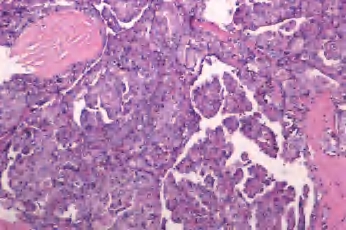

(1)滤泡亚型:由小至中等大小、不规则滤泡形成,实际上不含乳头结构,滤泡内含胶质,构成滤泡的上皮细胞有大而亮的核,含核沟和核内假包涵体。大约1/3此类肿瘤有包膜,预后与通常的乳头状癌相似(图3-44、图3-45)。

图3-44 甲状腺乳头状癌,滤泡亚型

图3-45 甲状腺乳头状癌,滤泡亚型